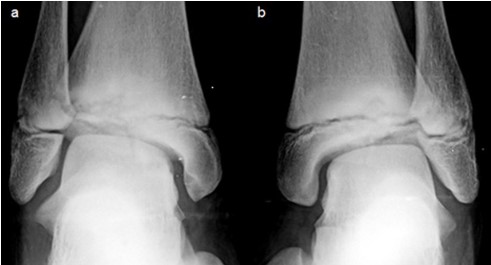

An MRI of the right ankle was performed showing fragmentation of the distal tibial epiphysis with erosion and bone marrow edema of the epiphysis and adjacent metaphysis. A consequent osteochondral lesion of the talar dome was also noted (Figure 2).

Figure 2: Sagittal T1 (a), coronal T1 (b) and coronal fat suppressed PD (c) weighted images of the right ankle show fragmentation of the tibial epiphysis and edema of the epiphysis and metaphysis. Note the consequent osteochondral lesion of the talar dome.